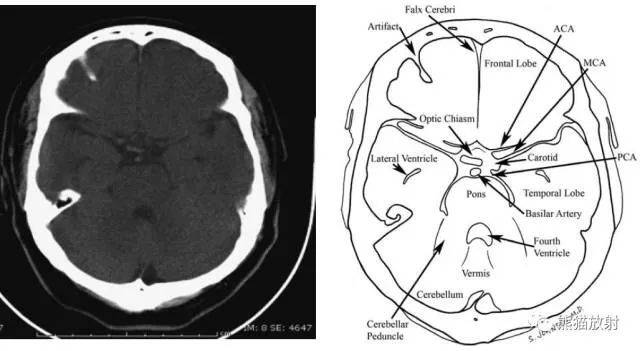

从前至后:大脑镰、伪影、额叶、视交叉、大脑前(ACA)、大脑中动脉(MCA)、颈动脉、基底动脉、侧脑室、脑桥、颞叶、四脑室、小脑蚓、小脑脚。

从前至后:大脑镰、额叶、外侧裂池、颞叶钩回、视交叉、基底池、中脑、大脑脚、小脑蚓、小脑、矢状窦。